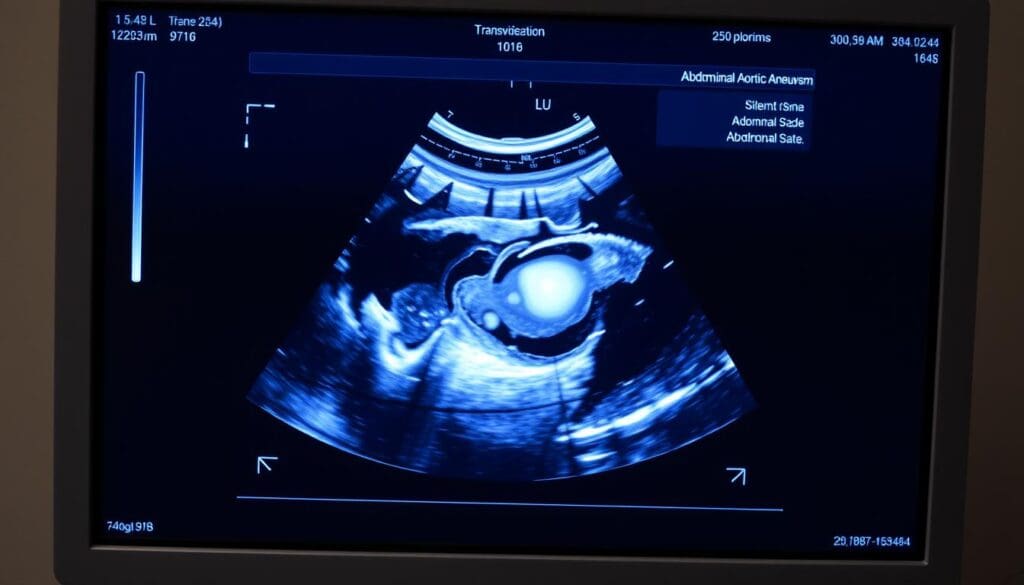

Healthcare providers use ultrasound screening for abdominal aortic aneurysm. This helps find aneurysms before they become dangerous.

Ultrasound is the top choice for finding abdominal aortic aneurysms. It’s safe and works well. This makes it key in keeping people healthy.

Ultrasound is great for checking for AAA because it’s easy on the body. It doesn’t hurt and doesn’t carry risks. Plus, it’s easy to get and not too pricey.

Ultrasound is very good at finding AAA. It’s about 95-100% accurate. This means it catches most problems.

Ultrasound screening for abdominal aortic aneurysms needs precise methods and protocols. This ensures we get accurate aorta measurements. We will look at the standard ultrasound views, how to measure properly, common challenges, and what to document. These are key for good AAA screening.

To get a clear view of the aorta, we use specific ultrasound views. The anterior-posterior (AP) view is key for measuring the aorta’s diameter. We also check the aorta’s shape and any swelling with transverse views.

Getting the aorta’s diameter right is critical. We measure from outer wall to outer wall, straight across the aorta. This way, we get the aorta’s biggest diameter, which is important for spotting AAAs.